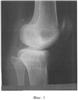

Способ проиллюстрирован сделанными в процессе лечения рентгенограммами нижней левой конечности (в разогнутом состоянии) больной М.:

Фиг.1 – боковая проекция (вид сбоку) до лечения;

В СарНИИТО больной было проведено обследование. На рентгенограмме левой конечности в боковой проекции (фиг.1) зафиксировано переразгибание коленного сустава со смещением в сагиттальной плоскости мыщелка голени кзади на 8 мм, что свидетельствует о подвывихе и рекурвации.